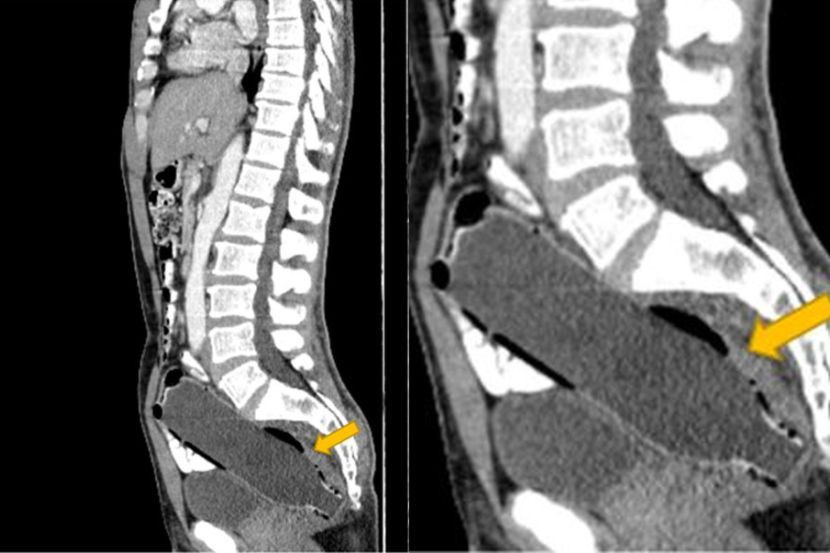

Laporan itu menyatakan bahawa lelaki berkenaan tidak kelihatan sakit apabila pemeriksaan pertama pada Februari, tetapi imbasan ultrasound mengesan bendasing tersumbat dalam duburnya.

Botol bersaiz 193 milimeter (mm) panjang dan 47mm dan berada 'di kawasan 10mm dari persimpangan anorektal tanpa sebarang tebukan yang jelas'.